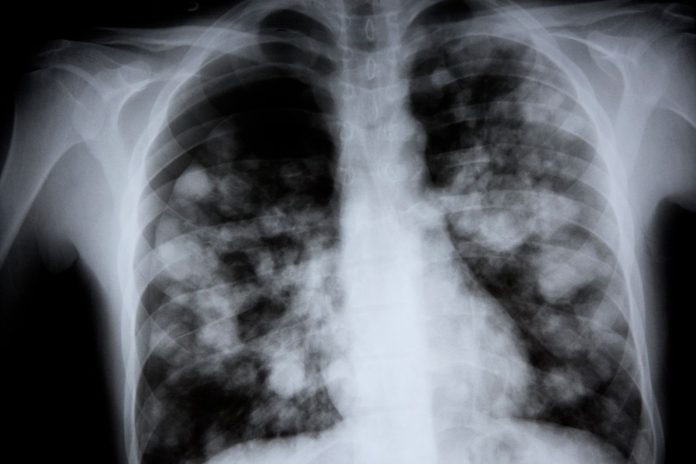

Sa i përket termit “mushkëria e bardhë”, ai nuk është një term mjekësor. Pneumonia mund të shfaqet në grafi si njolla të bardha, që tregojnë inflamacionin ose mbledhjen e lëngjeve si pasojë e infeksionit. Zakonisht, duke qenë se mushkëritë janë të mbushura me ajër, ato nuk e bllokojnë shumë rrezatimin dhe duken të errëta. Një grafi e mushkërive e tëra e bardhë është e rrallë dhe do të tregonte një mushkëri të kolapsuar ose një problem tjetër serioz.